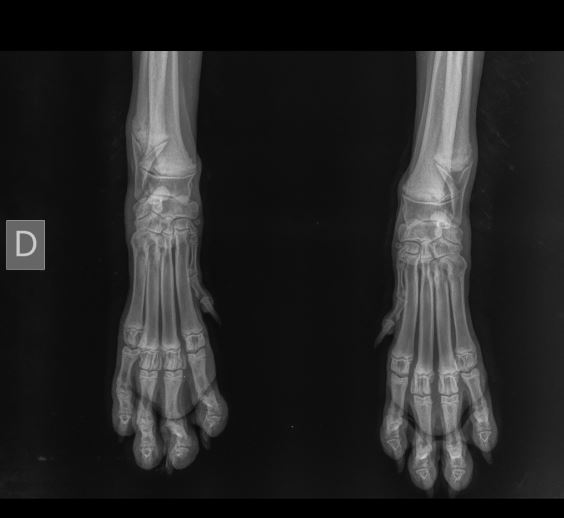

Ingresa a consulta una hembra canina de raza Bernesse Mountain Dog de 5 meses con molestia marcada a la marcha y al examen de extremidades anteriores.

Se obtiene radiografía D-P de segmento radioulnar distal con carpo y garra bilateral.

El diagnóstico radiológico de importancia para este caso es:

d) Osteodistrofia hipertrófica